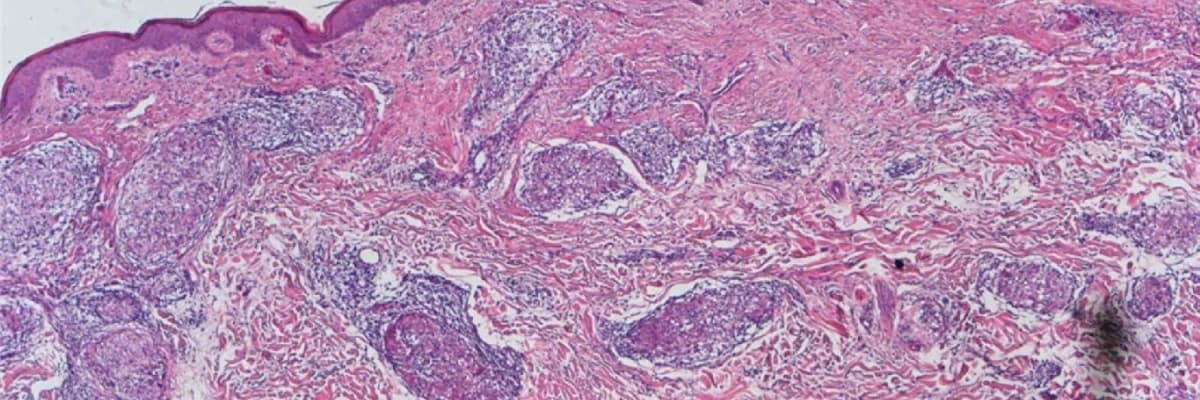

Sarkoidoz, bədənin müxtəlif toxumalarında mikroskopik iltihab hüceyrələrinin toplanması, yəni qranulomaların əmələ gəlməsi ilə xarakterizə olunan sistemik bir xəstəlikdir. Bu qranulomalar ən çox ağciyər toxumasında və lenfatik sistemdə inkişaf edir. Lakin xəstəlik yalnız bunlarla məhdudlaşmır; göz, dəri, qaraciyər və digər həyati orqanlar da bu prosesdən təsir lənə bilər.

Sarkoidozun diaqnozu kompleks bir yanaşma tələb edir. Müayinə prosesində xəstənin şikayətləri və fiziki müayinə nəticələri ilə yanaşı, müasir görüntüləmə üsullarından istifadə olunur. Diaqnozun dəqiqləşdirilməsi üçün tətbiq edilən metodlar bunlardır:

- Zəruri hallarda toxuma nümunəsinin götürülməsi (biopsiya).